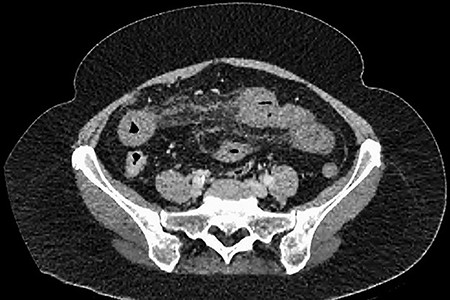

A 61-year-old female presented to a regional hospital with a 3-week history of intermittent diarrhoea, vomiting and generalized abdominal pain. She had a diffusely tender abdomen but was not peritonitic, and was shocked with a heart rate of 110 beats per minute, blood pressure of 89/45 mmHg and was peripherally cool. Her blood tests revealed a lactate of 7.2 mmol/L, which worsened to 7.8 mmol/L during resuscitation with intravenous fluids, and white cell count was 30.9 × 109/L, with an international normalized ratio (INR) of 1.4. She had an acute kidney injury with a creatinine of 119μmol/L and estimated glomerular filtration rate (eGFR) of 43 mL/min/1.73m2. Computed tomography (CT) revealed extensive thickened loops of non-enhancing small bowel with pneumatosis, moderate free fluid and a large splenic infarction. There was extensive thrombosis of the splenic vein and superior mesenteric vein extending into the portal vein to the level of the porta hepatis. Her background history included factor V Leiden and protein S deficiency, for which she had been non-compliant with warfarin during this illness. She had no surgical history (Figs. 1–5).

After initial assessment and fluid resuscitation, she was given broad-spectrum intravenous antibiotics and proceeded to emergent laparotomy. Intraoperative findings included an 80-cm segment of ischaemic jejunum, which was resected, with a laparostomy performed and transferred to the ICU. During laparotomy, a small 1.5-cm mass was observed arising from the antimesenteric border of the ischaemic segment, presumed to be a jejunal diverticulum and was included within the specimen. Peritoneal survey revealed splenic infarction but otherwise no other observed organ injury. She was noted to have a dusky-appearing right foot with no palpable peripheral pulse; however, arterial Doppler revealed midperoneal, posterior tibial and anterior tibial arterial stenoses, suggesting ischaemia due to a low-flow state. She was commenced on intravenous heparin. She returned to theatre 36 h later, at which time no further ischaemia was encountered, and anastomosis was performed and the abdomen subsequently closed. She recovered over a period of 1 week and was discharged home on warfarin.